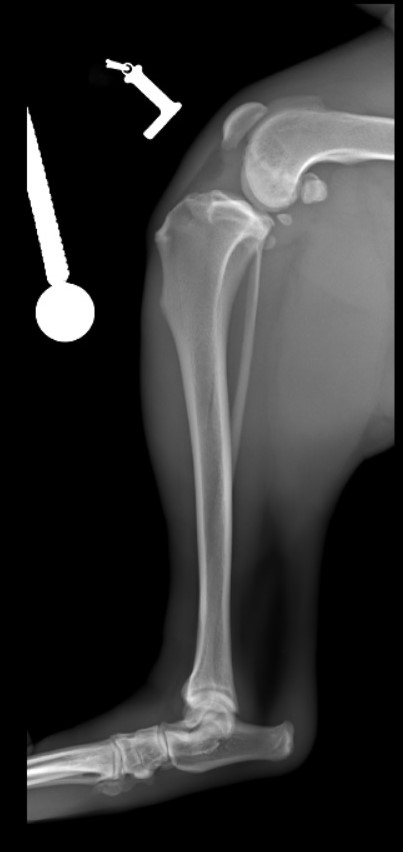

Nazywam się JJ :) Nigdy nie sądziłem, że będę potrzebował Waszej pomocy. Mam dopiero rok, urodziłem się 14 kwietnia 2019 roku. Lubię biegać, popiardywać, walczyć z odkurzaczem i dawać buziaczki człowiekom. Moi kochani opiekunowie przygarnęli takiego klopsa jakim jestem (a raczej byłem) ja... Mając zaledwie 4 miesiące zachorowałem na parwowirozę. Moje człowieki zrobili i oddali wszystko co mogli dać, abym wyzdrowiał. I tak się stało! Jednak zacząłem chorować bardzo szybko i po cichutku. Zaczęły boleć mnie moje tylnie nogi. Starałem się biegać, ale moje kolanka za bardzo bolały, więc ograniczyłem używania tylnich nóg do minimum podczas biegania. Żeby wejść na kanapę muszę bardzo się wysilić lub prosić moich człowieków, aby mi pomogli. Nie jestem w stanie wejść ani zejść po schodach bez odpoczynku. Moi kochani bracia i siostry (bo jesteśmy liczną rodzinką) patrzą na mnie z przykrością... Moje nietypowe siadanie na boku zaciekawiło domowników. Musiałem stworzyłem sobie garb, aby odciążyć nogi. Później pojawiły mi się guzki na prawej i lewej nodze. Na lewej nóżce guzek był troszkę większy, więc od razu pojechaliśmy do weterynarza. Niedobrze, bo guzki były już troszkę duże... Zapalenie, a może początek raka. Moja nowa Pani weterynarz zaczęła podejrzewać dysplazję biodrową. To mogłoby wyjaśnić moje “dziwaczne” siedzenie. Jednak nie była pewna, więc wysłała nas do specjalistów. Tam zrobili mi zdjęcia rentgenowskie i trochę mnie powyciągali. Bardzo mnie to bolało. Czułem wszystko, pomimo Jasia, którego dostałem. WERDYKT: Ześlizg główek w kościach kolana lewego i prawego o 33%, a to podobno bardzo dużo. Moje guzki to skutek rozlanego płynu zapalnego w kolanach. Moje lewe kolano choruje bardziej niż prawe. Jak się okazało nie urodziłem się z tym, ani nie jest to genetyczne. Po prostu zachorowałem na to. Moje kochane człowieki dostały dwie opcje.

Jedna to: operacja w kosztach 3 850,00 zł za jedną nogę (i to jak najszybciej...), a druga opcja to: amputacja kończyn.